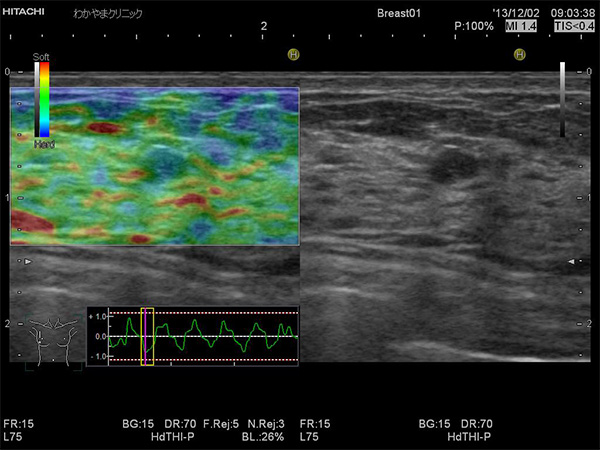

エラストグラフィとは、超音波検査でしこりの硬さを画像化する技術です。

力を加えたとき、柔らかいものは大きな変形を生じますが、硬いものはほとんど変形しません。

その変形の程度を色で表したものがエラストグラフィで、周囲よりも硬い部分は青く表示されます。

がん組織は、周辺組織より硬い場合が多く、しこりの硬さを知ることは診断の一つの重要な情報となります。